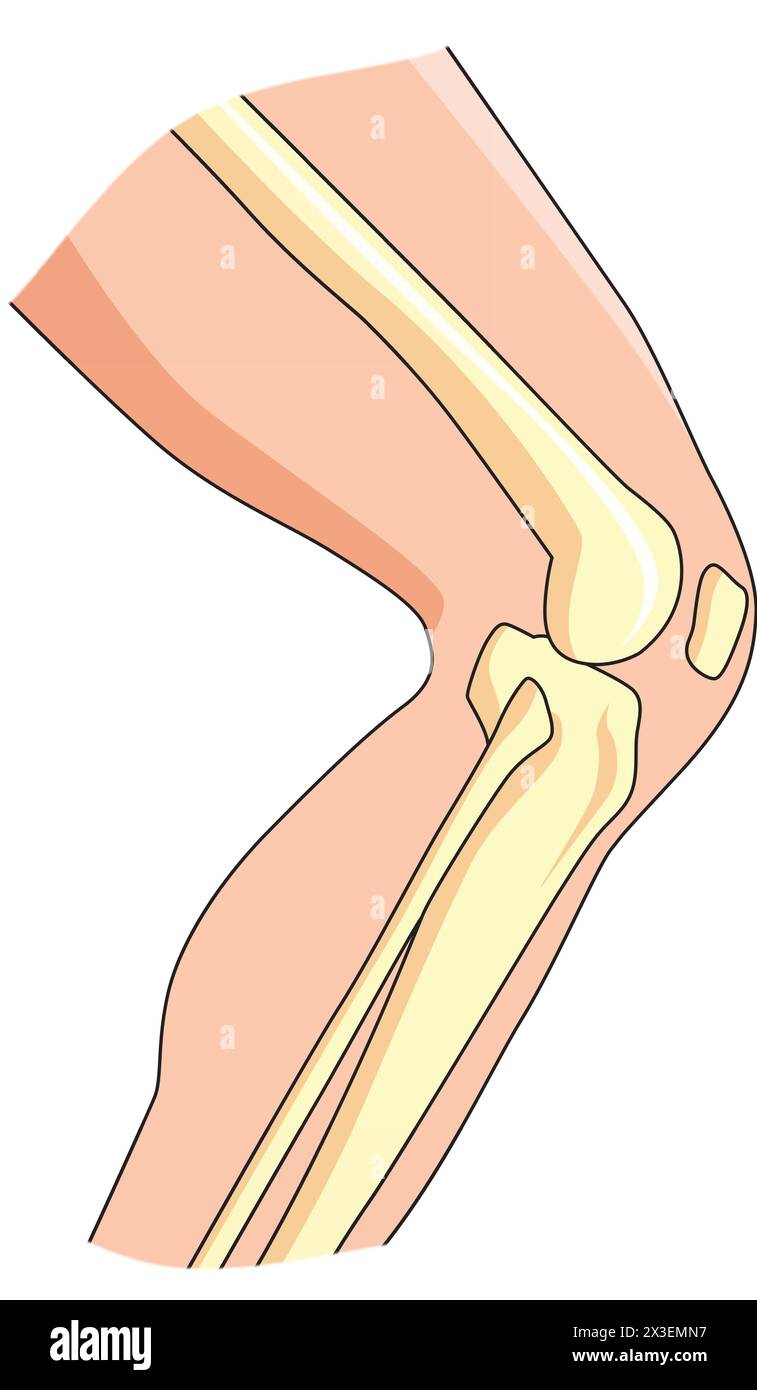

RF2AYYBRJ–Articulations humaines, articulation du genou, articulation du coude, articulation de la cheville, poignet. Vecteur orthopédique médical de l'ensemble. Anatomie orthopédique articulaire humain et illustration icône jambe et articulation de la main

RF2X200ED–L'anatomie de l'articulation de la cheville. Région talocrurale ou os sauteur. Partie du corps humain où le pied et la jambe se rencontrent. Fascia plantaire et tendon d'Achille

RFTDDFWM–Les blessures du ménisque d'illustration vectorielle médical isolé sur fond blanc, la déchirure du ménisque